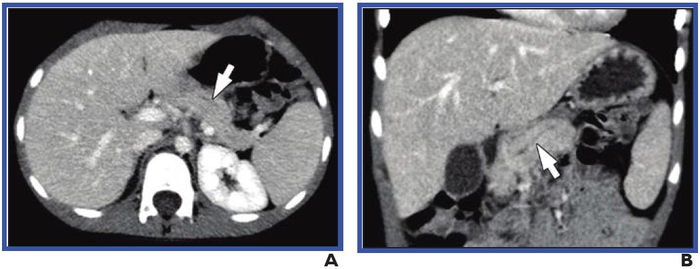

Leesburg, VA, March 8, 2022 According to an open-access Editor’s Choice article in ARRS’ American Journal of Roentgenology ( AJR ) , interobserver agreement proved generally fair to moderate for most CT and MRI findings of chronic pancreatitis in children.

In Trout et al.’s retrospective study, CT or MRI examinations performed in children with chronic pancreatitis were submitted by six sites participating in the INternational Study Group of Pediatric Pancreatitis: In search for a cuRE (INSPPIRE) consortium. One board-certified pediatric radiologist from each of the six sites participated in independent image review. Three radiologists independently reviewed only CT examinations, whereas three other radiologists independently reviewed just MRI examinations. While measuring pancreas thickness and duct diameter, reviewers evaluated 13 categorical subjective features: 12 on both CT and MRI, 1 on CT only, 1 on MRI only.

In this study of six sites in the INSPPIRE consortium, interobserver agreement for findings of chronic pancreatitis in children was relatively high for CT for the presence of parenchymal calcifications (κ=0.81), pancreatic duct dilation (κ=0.63), and atrophy (κ=0.52); and for MRI for main and side branch pancreatic duct findings (κ=0.64-0.74).

Noting that duct findings showed the highest levels of agreement for both modalities, “agreement for subjective findings of atrophy was moderate, and agreement for parenchymal thickness (a quantitative measure of atrophy) depended on the location of measurement, with the best agreement observed in the pancreatic body,” the authors of this AJR article concluded .